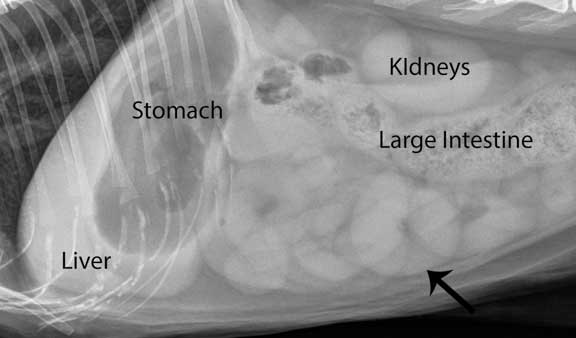

A labeled abdominal radiograph of a normal cat. The arrow points to the small intestine.

Another labeled normal cat lateral abdominal X-Ray

L- Liver

S- Stomach

K- Kidneys

S.I.- Small Intestines

L.I.- Large Intestines

U.B.- Urinary Bladder

F- Feces in the colon